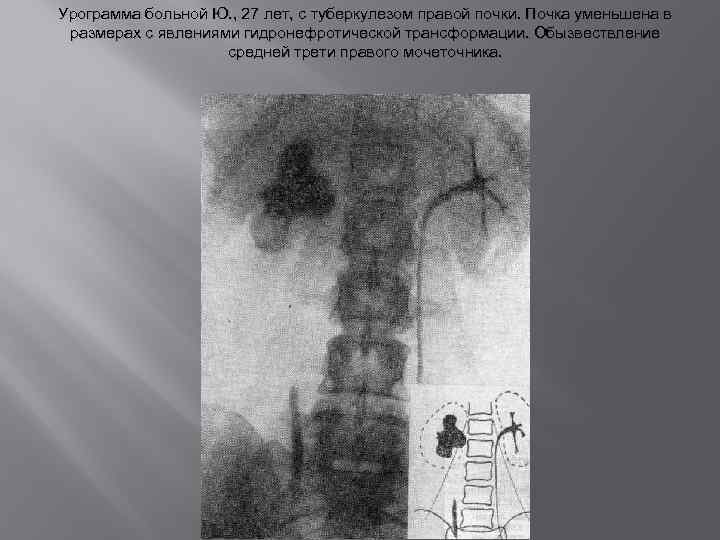

Диагностика • Обследование больного начинают с клинического анализа мочи. характерна кислая реакция мочи. Протеинурия при туберкулезе почки бывает в пределах 0, 033— 0, 99%, сопровождаясь незначительной микрогематурией • Туберкулезные микобактерии в моче обнаруживают методом микроскопии осадка, методом микроскопии обогащенного осадка — флотации, методом флюоресцентной микроскоп пии осадка, методом посева на различные питательные среды и путем заражения морской свинки мочой. Самым достоверным из указанных методов является посев мочи на питательные среды и заражение морской свинки • На основании обзорной рентгенограммы удается в подавляющем большинстве случаев установить диагноз почечнокаменной болезни. Характер проекции контуров почек позволяет судить об их величине (аплазия, гипоплазия, гипертрофия, сморщивание), о состоянии околопочечной жировой клетчатки (паранефрит • После обзорной рентгенографии производят экскреторную урографию. Для этого вида исследования требуется наличие удовлетворительной функции почек — нормальный уровень остаточного азота в сыворотке крови, максимальный удельный вес мочи пробе по Зимницкому не ниже 1014, отсутствие клинических признаков почечной недостаточности, массивной протеинурии и цилиндрурии.

Диагностика • Обследование больного начинают с клинического анализа мочи. характерна кислая реакция мочи. Протеинурия при туберкулезе почки бывает в пределах 0, 033— 0, 99%, сопровождаясь незначительной микрогематурией • Туберкулезные микобактерии в моче обнаруживают методом микроскопии осадка, методом микроскопии обогащенного осадка — флотации, методом флюоресцентной микроскоп пии осадка, методом посева на различные питательные среды и путем заражения морской свинки мочой. Самым достоверным из указанных методов является посев мочи на питательные среды и заражение морской свинки • На основании обзорной рентгенограммы удается в подавляющем большинстве случаев установить диагноз почечнокаменной болезни. Характер проекции контуров почек позволяет судить об их величине (аплазия, гипоплазия, гипертрофия, сморщивание), о состоянии околопочечной жировой клетчатки (паранефрит • После обзорной рентгенографии производят экскреторную урографию. Для этого вида исследования требуется наличие удовлетворительной функции почек — нормальный уровень остаточного азота в сыворотке крови, максимальный удельный вес мочи пробе по Зимницкому не ниже 1014, отсутствие клинических признаков почечной недостаточности, массивной протеинурии и цилиндрурии.